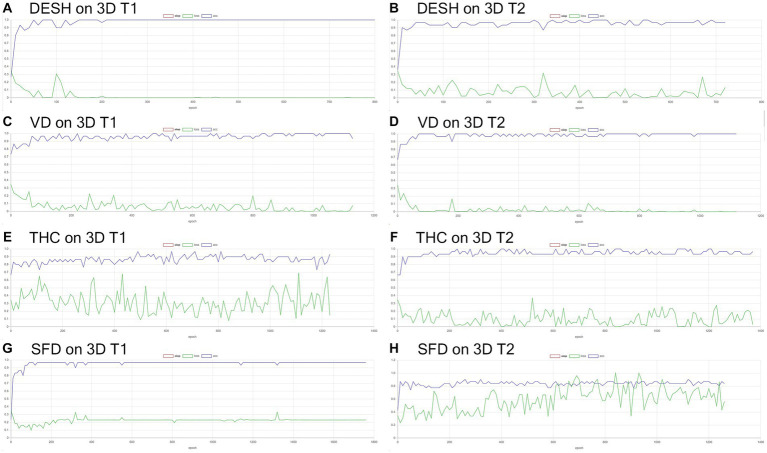

Volumetric semantic segmentation

Training and internal validation of the 3D U-Net model for semantic segmentation were repeated over 1,000 times (Figures 4–7; Supplementary Figures S1, S2). Overall, the intracranial CSF space, total ventricles, total SAS, Sylvian fissure and basal cistern, and the high-convexity SAS were segmented fully automatically from 3D T1-weighted (Figure 8) and T2-weighted MRIs (Figure 9). There was no significant difference between manually and automatically segmented volumes of the total ventricles, total SAS, high-convexity SAS, and Sylvian fissure and basal cistern (Table 3). Among the segmented regions, the mean Dice scores for the total ventricles were highest (0.85 from T1 and 0.83 from T2), those for the Sylvian fissure and basal cistern were second highest (0.70 and 0.69), and those for the high-convexity SAS were lowest (0.68 and 0.60). The mean Dice coefficient scores for all of the regions segmented from the T1-weighted image were superior to those from the T2-weighted image. The mean differences between the manually and automatically segmented volumes of the high-convexity SAS were smaller (T1 and T2; 3.6 mL and 4.2 mL) than those of the Sylvian fissure and basal cistern (5.3 mL and 8.3 mL).